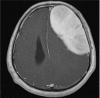

Giant Intracranial Solitary Plasmacytoma